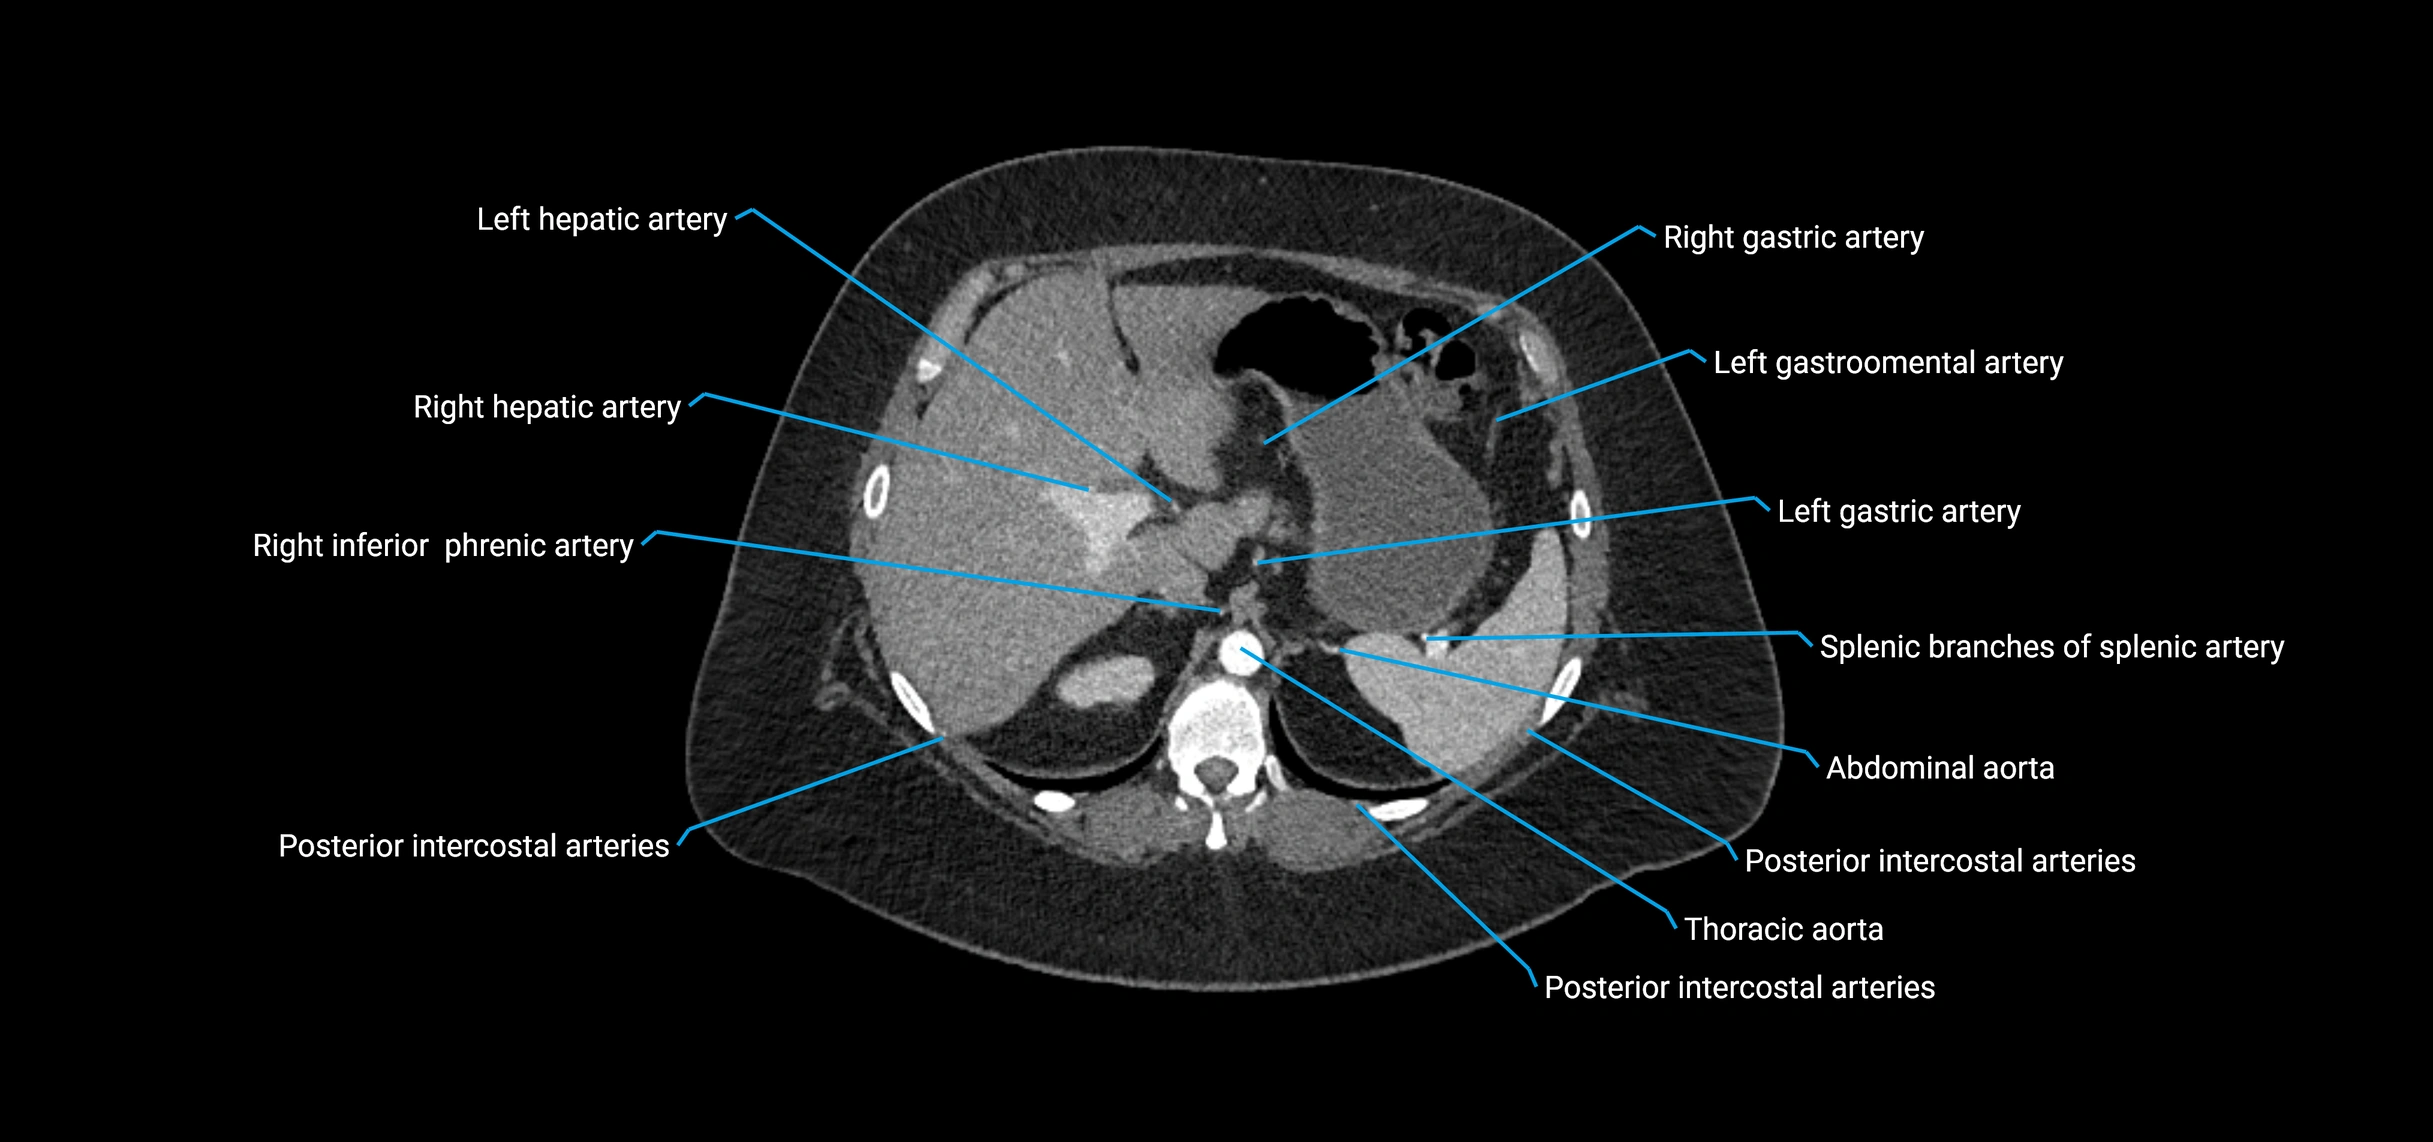

Contrast-enhanced CT (CTA):

• Gold standard for abdominal aortic imaging

• Provides excellent detail of lumen, wall, aneurysm, thrombus, and branch vessels

• Multiplanar and 3D reconstructions help in aneurysm measurement, stent graft planning, and dissection evaluation